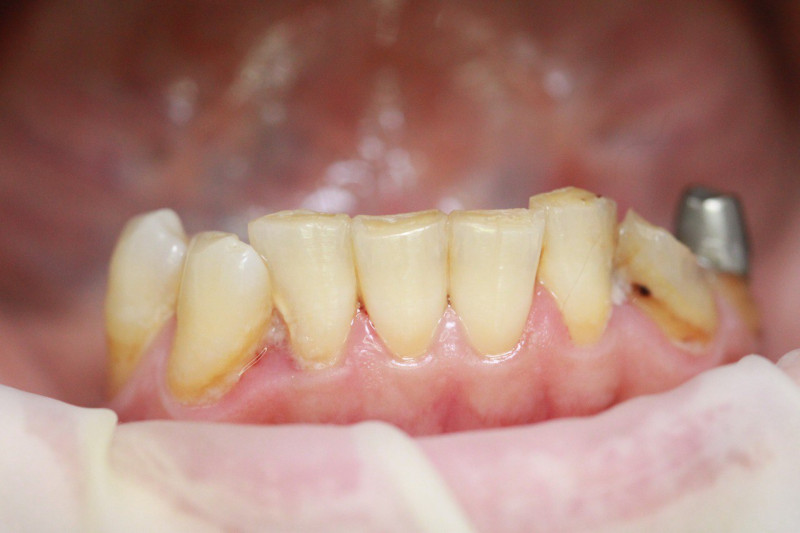

Index Dual — это диагностический маркер, предназначенный для идентификации зрелости зубных отложений. В современной стоматологии это «детектор лжи» для пациента и навигационная карта для врача. Без использования подобных средств эффективность профессиональной чистки снижается, поскольку до 30% налёта остаётся незамеченным в межзубных промежутках и поддесневой зоне.

• Для пародонтологов: Чёткая дифференциация старого налёта (синий цвет) указывает на зоны риска развития пародонтита и локализацию патогенной флоры.

Index Dual работает по принципу селективного окрашивания: свежий налёт (до 24 часов) становится розовым, а зрелый кариесогенный налёт (более 24 часов) — синим.